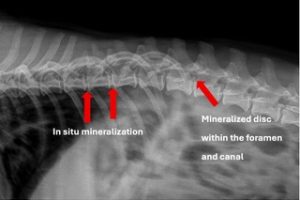

Presentation: Signalment: 4-year-old male neutered Corgi History: No prior medical conditions. 10-day history of paraplegia. Physical findings: No significant joint abnormalities. Mentally appropriate. Forelimbs normal. Non-ambulatory paraplegic, extensor rigid …